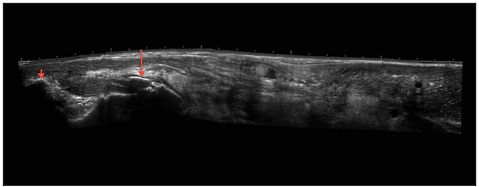

Because the triceps on his right arm looked unusual, the doctors made a scan of his arm. The scan showed that the man had torn his triceps, which you can see in the photo below, between the two red arrows.